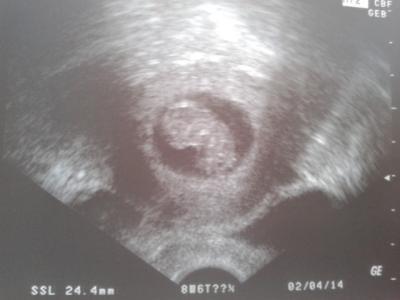

So ihr lieben, Ich bin zuruek vom FA! Und es war wirklich toll. Das geraet meiner aerztin scheint nicht das neuste zu sein-meinte sie, aber wir konnten unsern kleinen krümel trotzdem schon erkennen. Und dann hat er sich sogar bewegt und wir konnten arme und beine als kleine gnubbel sehen! sah aus wie ein kleines gummibaerchen. Das herzchen hat brav geschlagen und sie meinte, es ist alles zeitgerecht entwickelt. Oh man ich kann es noch gar nicht fassen und hab das gefuehl es noch gar nicht zu realisieren.

Bild zu zurueck vom FA...mit Bild - Forum für April - Mamis